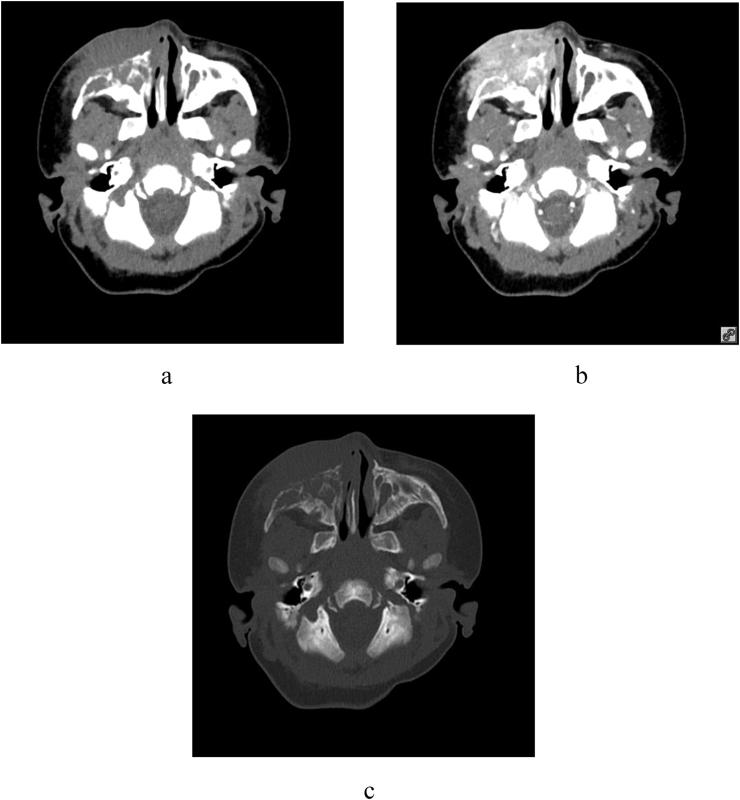

The mean age of the 27 patients was 105 ± 80.27 days. Twenty-two (81.5%) of these patients had Kasabach-Merritt phenomenon. Most KHEs were located in the trunk and/or extremities (22/27). Ultrasonography showed heterogeneous echogenicity and/or striated hypoechoic bands with abundant or patchy blood flow within the tumor. On plain computed tomography (CT), they appeared as heterogeneous lesions isodense with the muscles, with a CT value of 29.58 ± 11.53 HU. In the arterial phase, the KHEs showed striated or lamellar heterogeneous enhancement, with a CT value of 153.91 ± 52.11 HU after enhancement. All KHEs showed uneven and high signal intensity on T2-weighted imaging, mixed high and low signal intensity on fat-saturated images, and no significant diffusion restriction on diffusion-weighted imaging.

KHEs can occur in various locations and present as highly infiltrative and heterogeneous masses that can invade the skin, adjacent muscles, and bones. A vascularized mass with purpuric skin changes, with uneven and high T2WI signal is highly suggestive of the diagnosis of KHE.

27例患者的平均年龄为105±80.27天。其中22例(81.5%)患者出现卡萨巴赫-梅里特现象。大多数KHE位于躯干和/或四肢(22/27)。超声检查显示肿瘤内部回声不均匀,可见条纹状低回声带,血流丰富或呈片状。平扫计算机断层扫描(CT)显示病变与肌肉等密度,密度不均匀,CT值为29.58±11.53 HU。动脉期,KHE呈条纹状或片状不均匀强化,强化后CT值为153.91±52.11 HU。所有KHE在T2加权成像上均表现为不均匀高信号,在脂肪抑制图像上呈高低混合信号,在扩散加权成像上无明显扩散受限。

KHE可发生于不同部位,表现为高度浸润性、不均匀的肿块,可侵犯皮肤、邻近肌肉和骨骼。出现皮肤紫癜改变的血管化肿块,T2WI信号不均匀且高,高度提示KHE的诊断。